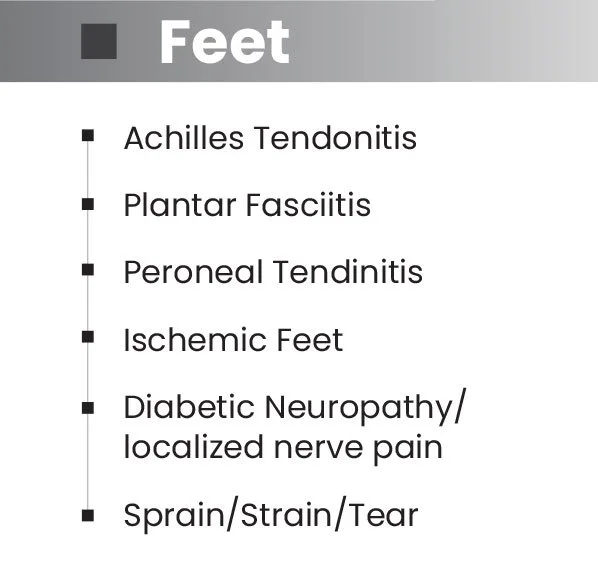

Effective Pain Reduction Across a Broad Range of Conditions.

Achilles Tendonitis

Plantar Fasciitis

Back, neck, shoulder, elbow and knee pain